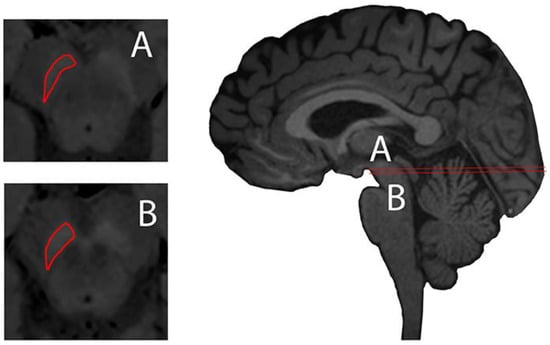

- Martin-Bastida, A. Nigral iron and neuromelanin imaging studies in Parkinson´s disease. Ph.D. Thesis, Medicine. Imperial College London, London, UK, 2019. [Google Scholar]

- Martin-Bastida, A.; Lao-Kaim, N.P.; Loane, C.; Politis, M.; Roussakis, A.A.; Valle-Guzman, N.; Kefalopoulou, Z.; Paul-Visse, G.; Widner, H.; Xing, Y.; et al. Motor associations of iron accumulation in deep grey matter nuclei in Parkinson’s disease: A cross-sectional study of iron-related magnetic resonance imaging susceptibility. Eur. J. Neurol. 2017, 24, 357–365. [Google Scholar] [CrossRef] [PubMed]